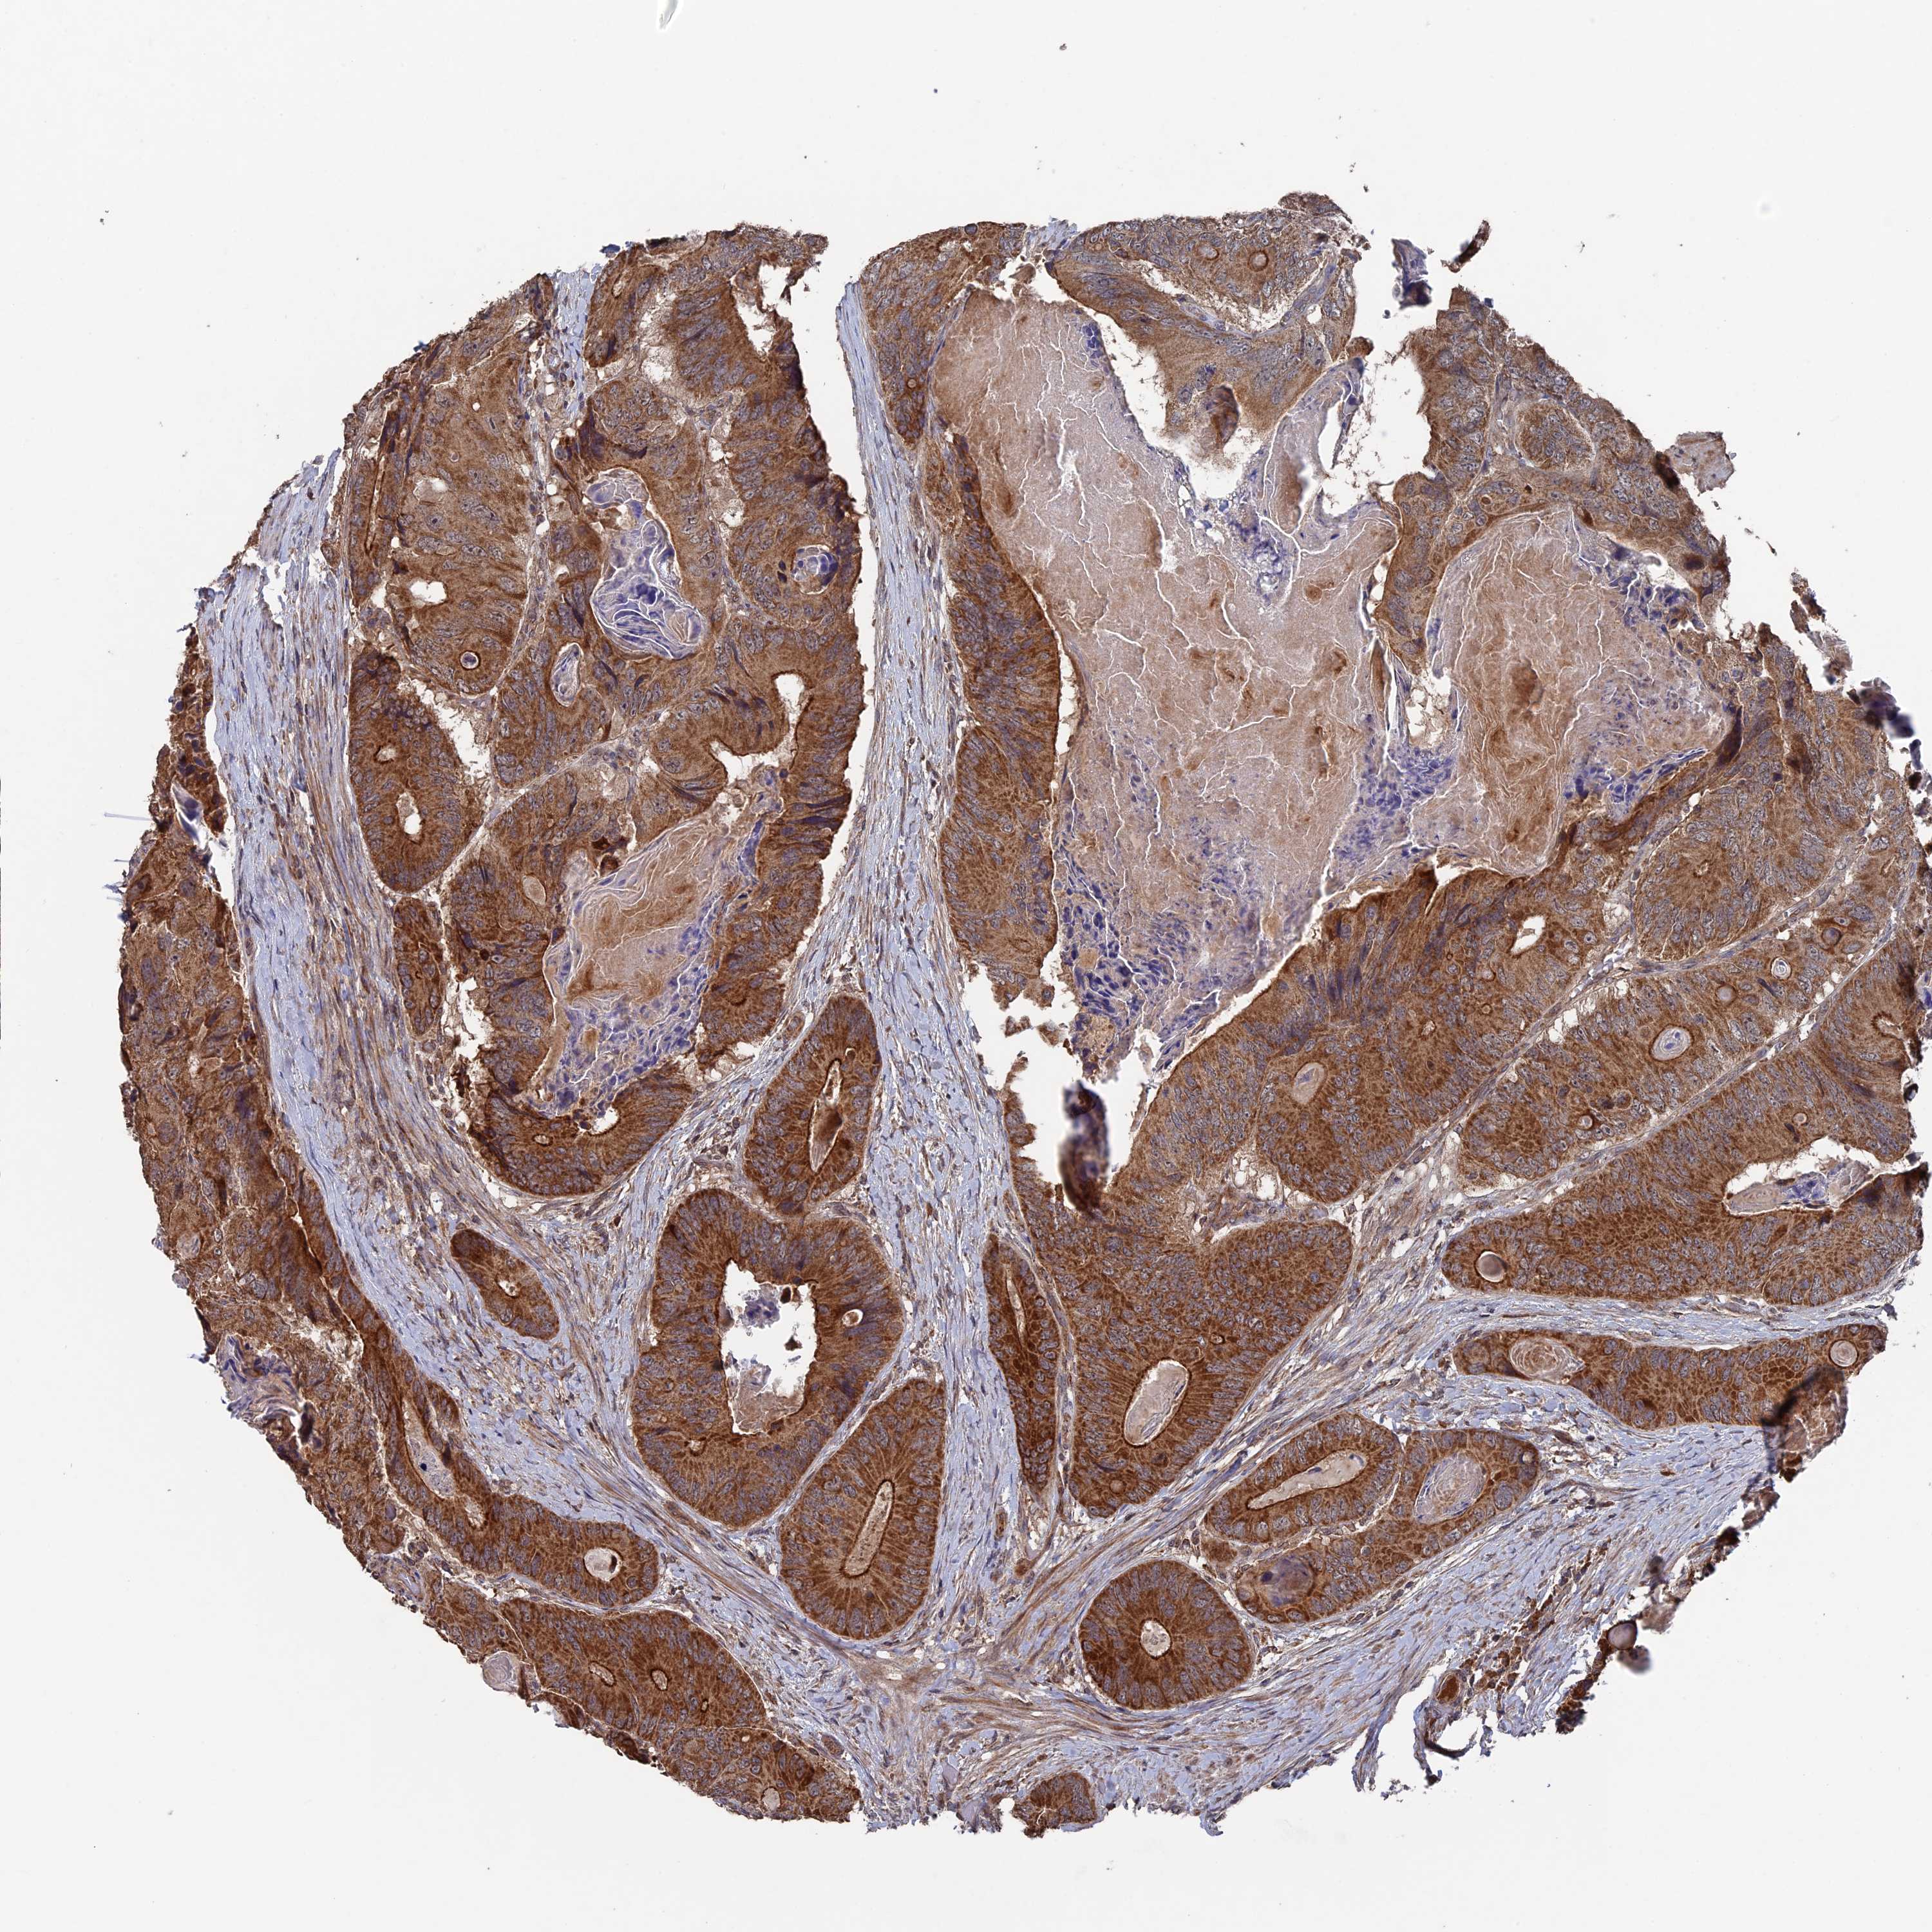

CANCER COLORECTAL CANCER Show tissue menu

Colorectal cancer

Human cancer

Colon adenocarcinoma